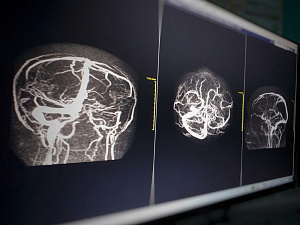

Диабетическая полинейропатия

Диабетическая полинейропатия (ДПН) – патогенетически связанное с сахарным диабетом сочетание синдромов поражения нервной системы. Частота среди лиц с СД 2 типа достигает 70-90%.

ДПН классифицируется в зависимости от преимущественного вовлечения в процесс спинномозговых нервов (периферическая нейропатия) и/или вегетативной нервной системы (автономная нейропатия).

Диабетическая дистальная симметричная сенсорно-моторная полинейропатия — самый частый вариант периферической диабетической нейропатии. Типичными симптомами являются ощущение жжения, «бегания мурашек», боли в голенях и стопах, ночные судороги мышц. При неврологическом обследовании выявляются ослабление ахилловых рефлексов, нарушение чувствительности по типу «носков» и «перчаток», снижение проприоцептивной чувствительности. Важно, что при поздней диагностики патологии развиваются такие осложнения язвы стоп, которые могут приводить к гангрене (диабетическая стопа) и часто к ампутациям. В лечении эффективны трициклические антидепрессанты (амитриптилин) в качестве обезболивающих препаратов, альфа-липоевая кислота и витамины группы В на фоне активного контроля уровня гликемии.

К основным клиническим проявлениям кардиоваскулярной автономной нейропатии относятся тахикардия покоя («фиксированный» пульс, часто ранний признак развивающейся ДПН), аритмии (нейропатическое удлинение интервала Q–T и др.), ортостатическая гипотензия, безболевая ишемия миокарда (БИМ), артериальная гипретензия (повышение активности симпатического отдела нервной системы, вызванное парасимпатической дисфункцией; отсутствие снижения АД в ночное время).

Методы диагностики кардиоваскулярной автономной нейропатии включают: исследование кардиоваскулярных рефлексов (тест Вальсальвы, тест Шелонга и др.), суточное мониторирование АД, холтеровское мониторирование ЭКГ, измерение корригированного интервала QT и дисперсии интервала Q.